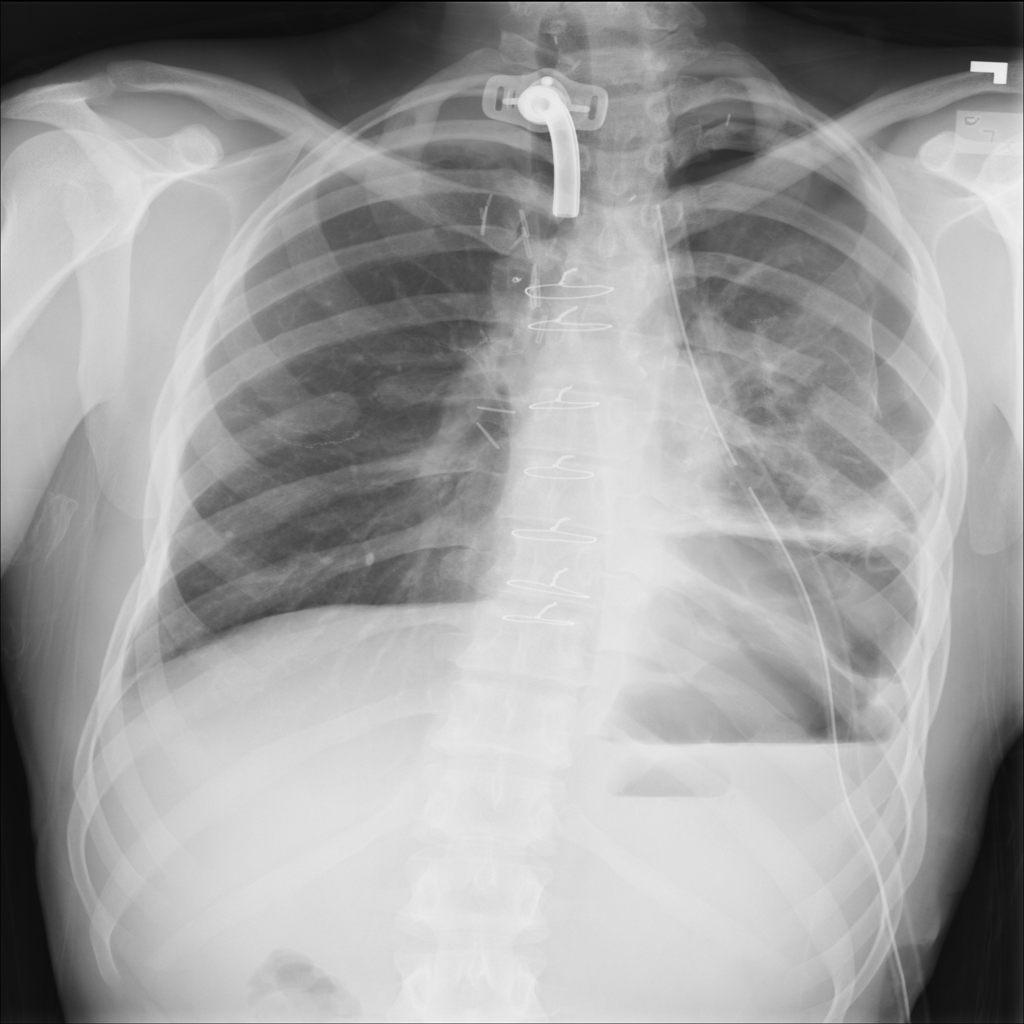

Showing up to 90 reference images for Pneumothorax.

PAT-4639 · IMG-012Pneumothorax

PAT-4639 · IMG-012

AP